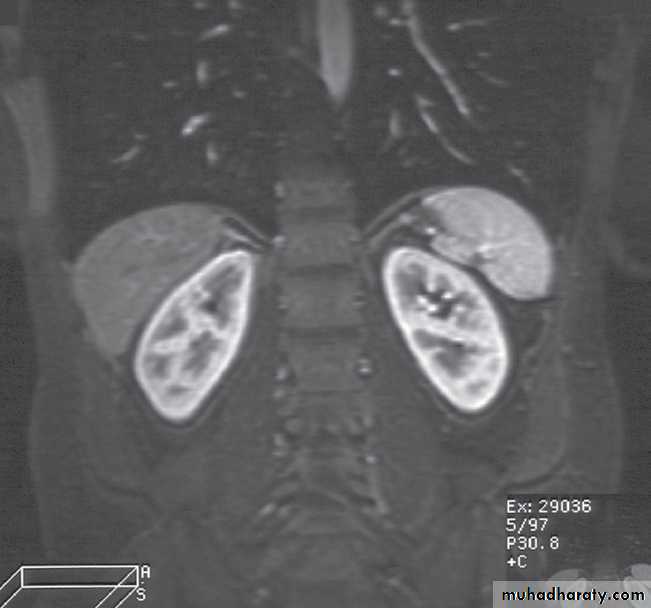

Normal magnetic resonance imaging

As with CT and ultrasound, the renal contours should be smooth. Corticomedullary differentiation is best seen on T1-weighted images and immediately following intravenous contrast enhancement with gadolinium .The renal collecting systems, ureters and bladder are best seen on T2-weighted images, as the fluid returns a high signal intensity .

Some normal variants are well demonstrated on MRI:

-Fetal lobulation & a column of Bertin (which is normal renal parenchyma that may look mass-like) .Special techniques